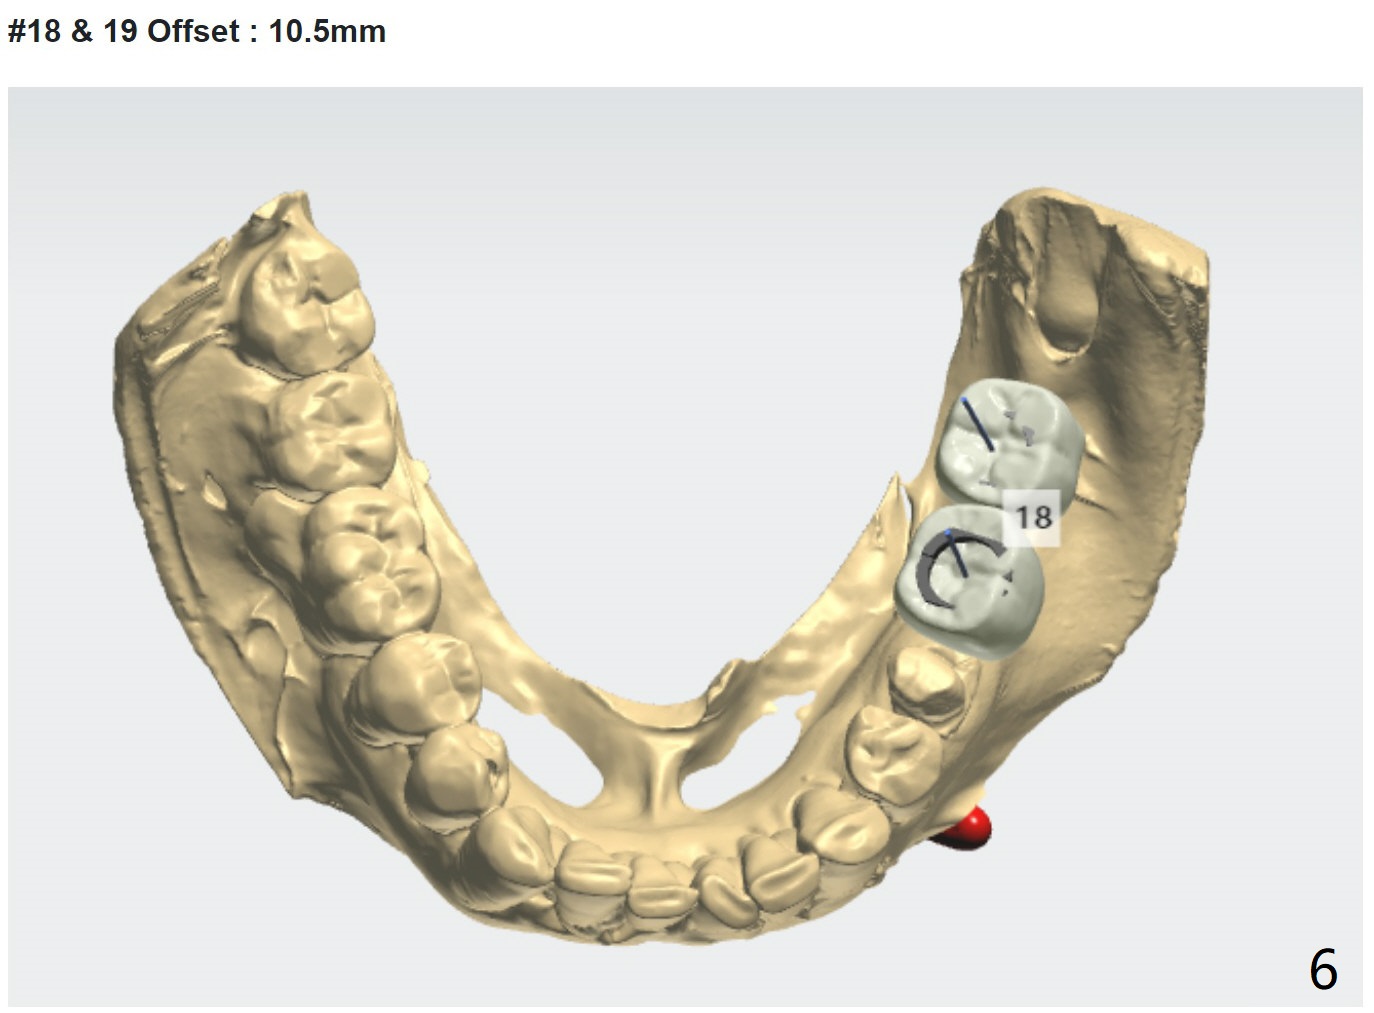

Distal Stop